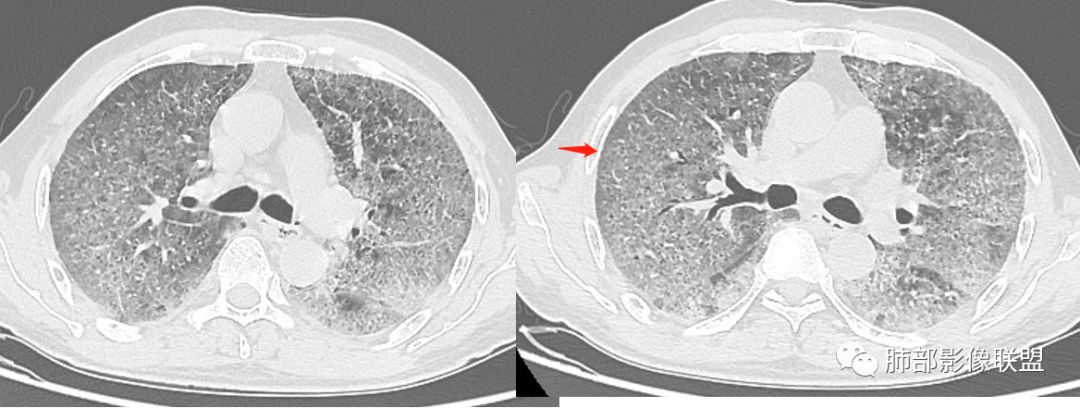

徐婕:双肺弥漫磨玻璃,铺路石,部分斑片实变。病程一年,血白细胞增高,考虑肺泡蛋白,合并双肺感染?鉴别腺癌

八爪:弥漫分布磨玻璃密度影,小叶间隔增厚,典型铺路石征,考虑PAP伴发感染性病变,鉴别特发性间质性肺炎,弥漫性腺癌,建议支气管灌洗;左肺上叶舌段不规则团片状阴影,显示不清,密切随访

小谢:慢性病程,无发热,双肺弥漫性病变,GGO,铺路石征,首先考虑PAP,鉴别肺腺癌

一米阳光:中老年男性,病程长。双肺弥漫性ggo,小叶间隔明显增厚,铺路石样改变,考虑PAP,鉴别pcp。建议支气管镜检查并灌洗。病史有尘肺接触史,排除尘肺合并结核

我心飞翔:中年男性,双肺弥漫磨玻璃影,铺路石征,病灶内可见扩张支气管,CEA高,血象高,黄痰,考虑PAP并感染,腺癌待排

郑氏刀刀:双肺弥漫性磨玻璃影,伴铺路石征,下叶为主,且见斑片实变影,白细胞高,结合执业史,尘肺,PAP伴感染,腺癌待排。

小景:双肺弥漫磨玻璃影,小叶间隔增厚,呈碎石路征。患者粉尘接触史,考虑PAP。左肺舌段病灶,抗感染无吸收,腺癌待排。

小赵:中老年男性患者。慢性病程,多次咳黄痰,治疗效果一般,反复发生。CT表现为双肺弥漫磨玻璃样改变,并呈细网格样铺路石状改变,上下肺无明显差异。双下肺为主多发渗出实变,边界不清,抗炎治疗后病变吸收不明显,局部似有进展。考虑肺泡蛋白沉积症基础上合并感染。肿瘤标志物高,中老年患者,肺炎型肺癌不除外。

碎石路征,下肺为主

南边:只有GGO+网格(小叶间隔增厚),然后就是分布的问题

1、GGO+网格——碎石路征

2、分布无特定位置,较随机

3、可有少许实变——部分与层厚有关

4、小叶间隔内静脉增粗

5、病灶较多时部分可见重力趋势

1.由于脂蛋白的沉积和占据,肺泡腔含气量减少,这是影像上较大范围“磨玻璃影”的基础。

2.由液体、细胞浸润和纤维组织造成的小叶间隔增厚是影像上多边形“铺路石征”的基础。

3.显眼的小叶间隔对病灶有阻挡作用是形成影像上“地图样改变”的基础。我们观察到的病灶与临近相对正常肺组织之间常常有比较清楚的分界。

这种表现颇具特征性。但有部分患者(1/4)仅有磨玻璃影而未显示小叶间隔增厚,这种情形我们很难将PAP列为第一诊断。